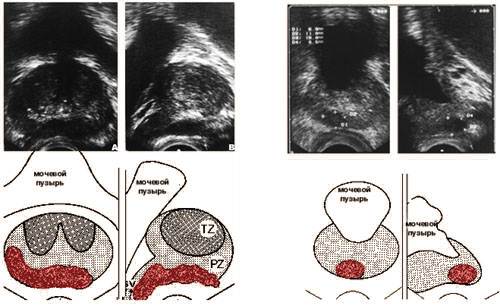

Трансректальная ультразвуковая томография.

Опухоль предстательной железы.